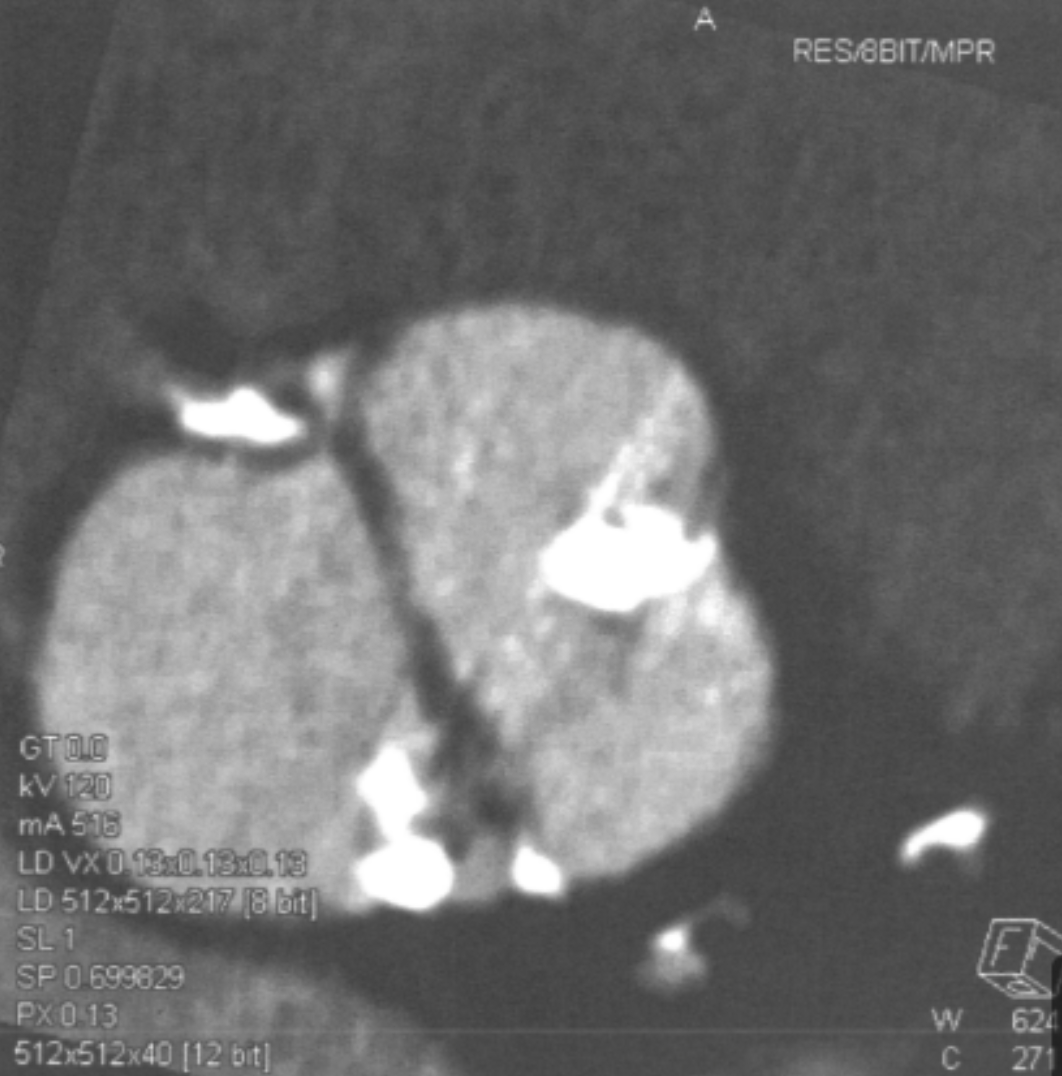

How can a myocardial perfusion defect be differentiated from an artifact?

Which are the best window width and window level for assessing myocardial perfusion defects, respectively?

WW: 200 / WL: 100

Which coronary artery distribution is affected by the perfusion defect displayed in the image?

LCx or RCA (depending on dominance)